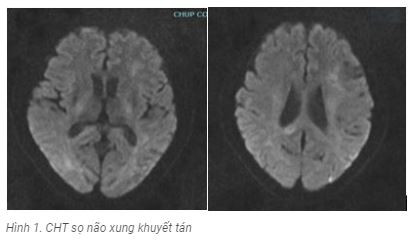

Bệnh nhân được khảo sát cộng hưởng từ sọ não, xét nghiệm dịch não tủy và các xét nghiệm cơ bản sàng lọc độc chất, bệnh chuyển hóa.

Kết quả CHT sọ : tổn thương tăng tín hiệu trên xung khuyết tán tổn thương chủ yếu vùng vỏ não thùy chẩm, đỉnh 2 bên ( hình 1); trên xung Flair tổn thương tăng tín hiệu vùng cuống não phải, dưới đồi phải, tổn thương chất trắng cạnh não thất 2 bên ( Hình 2).

Sau 5 ngày điều trị lâm sàng bệnh nhân có cải thiện hơn hết loạn thần, còn rối loạn trí nhớ, trả lời còn lẫn lộn thiếu chính xác, cơn co giật được kiểm soát, bệnh nhân được chụp lại CHT sọ não đánh giá tổn thương và xét nghiệm dịch não tủy lần 2 kết quả tổn thương trên flair không thay đổi, nhưng tổn thương mới trên DWI hiện rõ ràng hơn; protein dịch não tủy 0,84 g/l; tế bào : 03 tế bào .